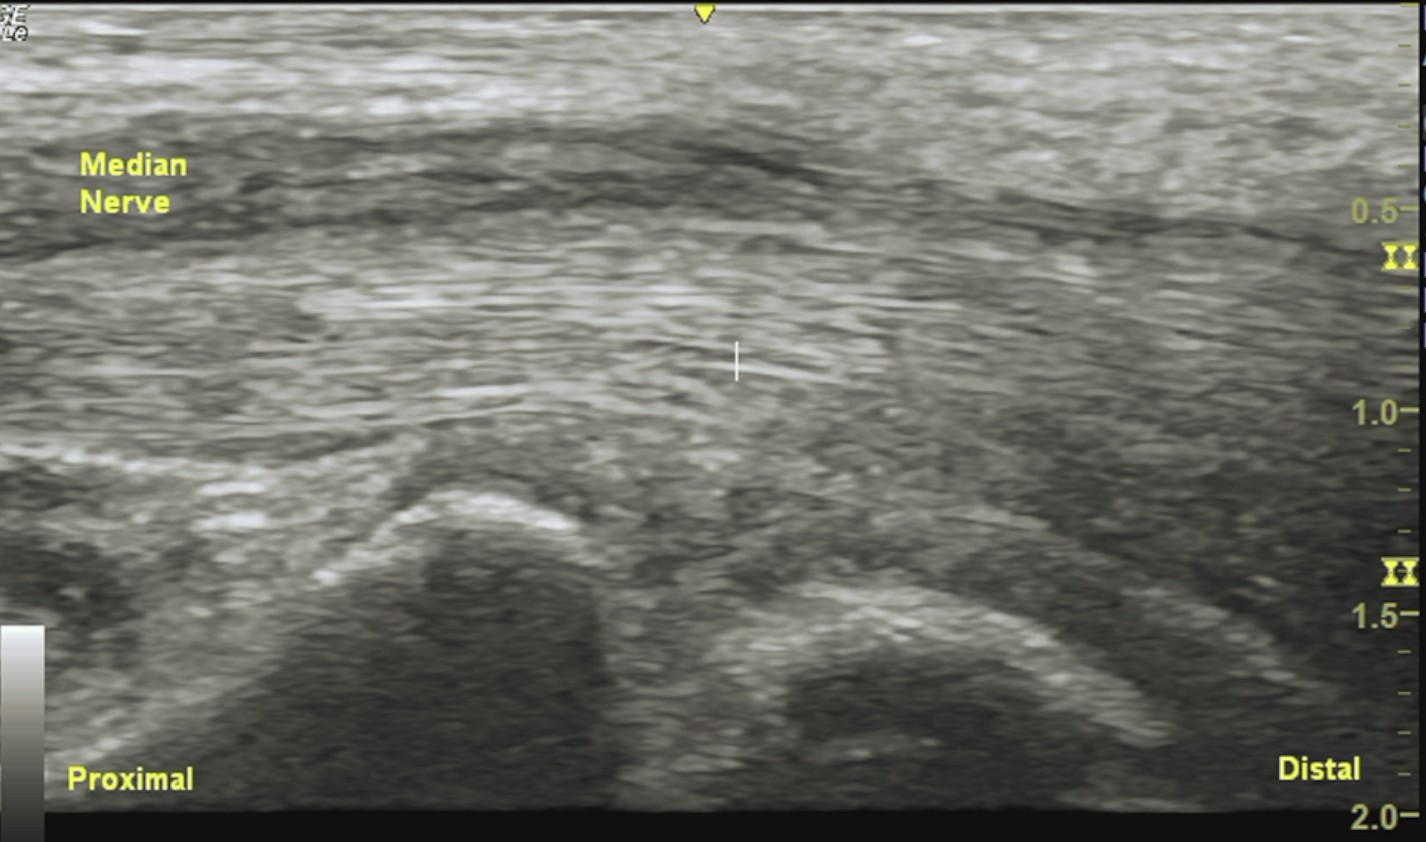

Labeled long axis view of the median nerve at the wrist demonstrating progressive distal tapering of the median nerve within the carpal tunnel, with surrounding homogeneous isoechoic soft tissue.

Unlabeled long axis view of the median nerve at the wrist.